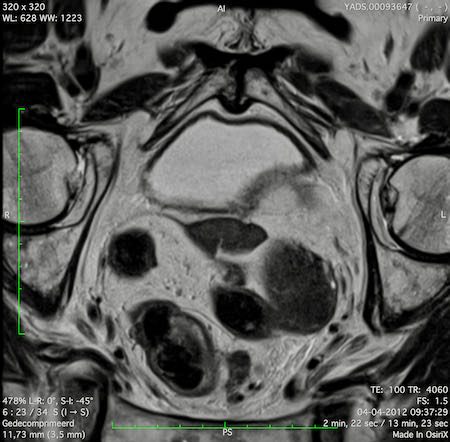

Hình ảnh

Các hình ảnh được cung cấp cho thấy ung thư biểu mô tế bào nhẫn với tình trạng dày lan tỏa thành trực tràng, hình ảnh bia bắn điển hình, và sự xâm lấn mỡ mạc treo trực tràng.